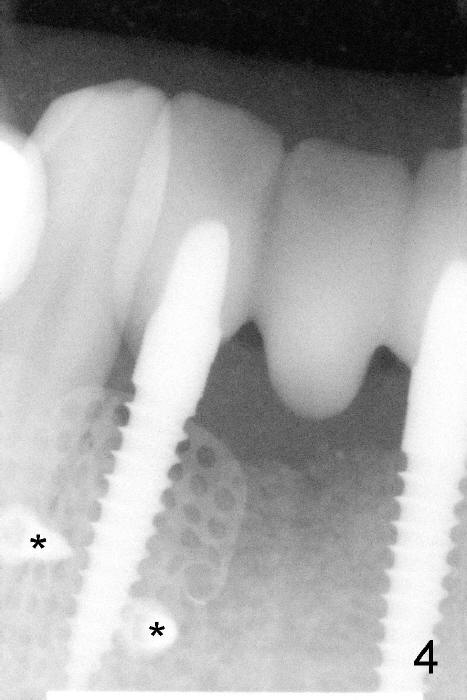

The coronal portion of the mesh is exposed with loss of bone graft granules. It appears that the mesh has lost its function. It is planned to be removed. PA is taken 16 days post placement of the mesh (Fig.4).

Fig.5 is taken following local anesthesia to show the exposed mesh, 22 days post placement. When the latter is removed, the exposed threads appear to be less (Fig.6, as compared to Fig.2). There is healthy granulation tissue growth apically (*). The patient is asymptomatic 1 month post mesh removal; there is no tenderness around exposed threads (Fig.7). Connective tissue graft is planned to cover the exposed threads through tunnel technique. Thread exposure appears less 3 months post mesh removal (Fig.8). There is infection when the region is not kept clean (Fig.9 (2.5 years post mesh removal)). The other 1-piece implant should have minor implant exposure (<). It appears that there is no thread exposure associated with the immediate implant at #28. Using smaller 1-piece implants (2.5 or 2.0 vs. 3 mm) with flap surgery should be able to prevent the complication. The 72-year-old phobic patient declines any further treatment. Two years later, she agrees to have treatment because of repeated infection (Fig.10). Impression has been taken for stent. After sectioning FPD and removing the infected implant (Tatum), a smaller implant will be placed in between the implants. If her vein is not too small, blood will be drawn for PRF.